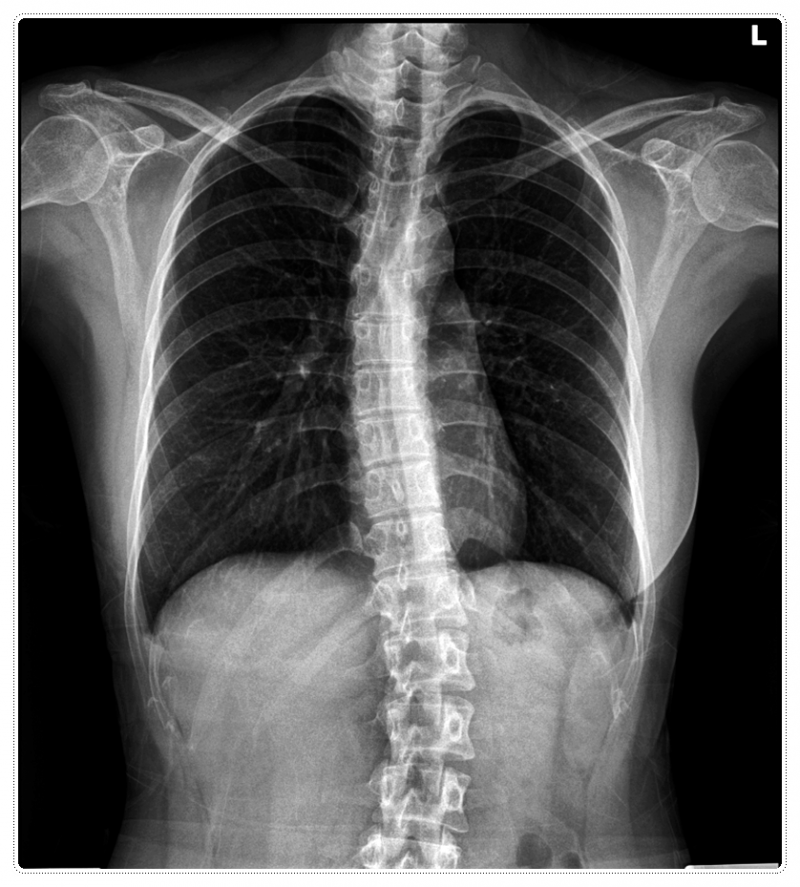

![]()